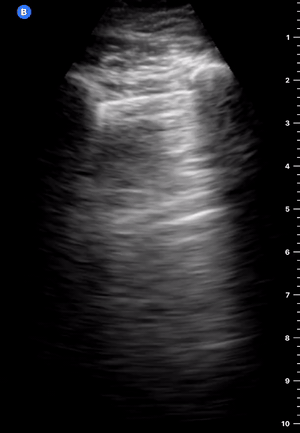

The M mode is far from essential but can be helpful in the interpretation if you struggle to identify sliding in B-Mode. A ‘seashore image’ will be seen in the normal lung, whereas a ‘barcode image’ will appear in absence of lung sliding. Remember, absent lung sliding by itself is not diagnostic of pneumothorax.